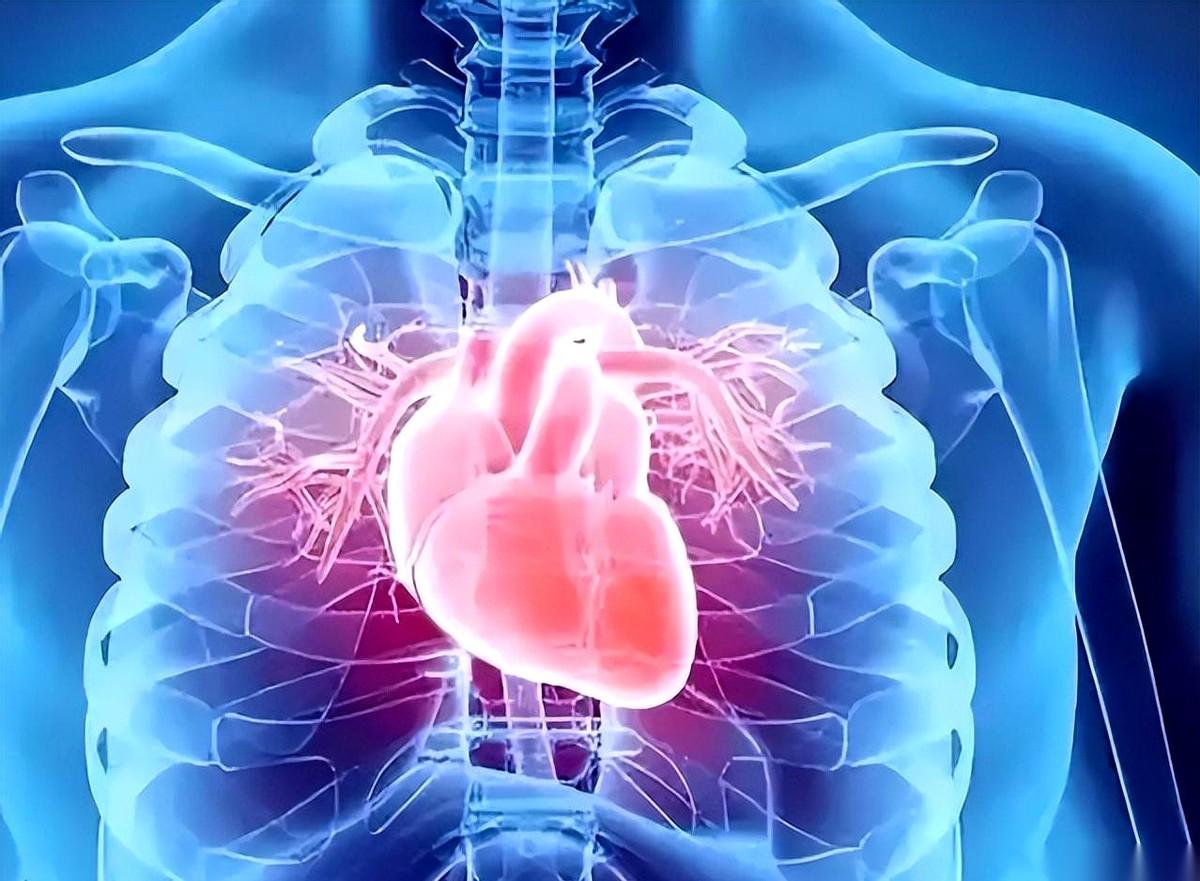

心脏“咯噔”一下,像漏了一拍。 尤其是一躺下,感觉整个胸口都不属于自己了。 完蛋,是心梗的前兆吗?脑子里警报瞬间拉满。 相信我,这感觉,很多人都有过。 然后就是一通折腾,跑去医院挂号、排队、心电图、心脏彩超……最后医生云淡风轻地告诉你:别紧张,功能性早搏,回去好好休息。 啥叫“功能性”? 说白了,就是你的心脏零件没坏,但线路有点接触不良,信号偶尔短路。 可为什么会短路? 这才是问题的根。 后来我才琢磨明白,这哪是心脏在罢工,这他妈是身体在拉警报啊。它在告诉你:主人,我缺东西了! 缺什么?三样东西最关键:钾、镁、钙。 钾,就是心脏的“节拍器”。它稳不住,心跳就容易乱来。但这家伙脾气大,不能瞎补,补多了更要命,得让医生说了算。 镁,是心脏的“镇定剂”。很多人焦虑、失眠、心慌,其实是缺镁。它就像个和事佬,帮你稳住神经,不让心脏瞎激动。多吃点深绿叶菜、坚果、粗粮,比啥都强。 钙呢,管的是心跳的“力气活儿”。力气太大或太小,都不对。 你看,心脏这东西,精贵得很。 它不喜欢你熬夜喝酒刺激它,更不喜欢内部失衡,缺这缺那。 所以啊,下次再“咯噔”一下,先别自己吓自己。 你得学会听它说话。 它那一下,不是想吓你,是想告诉你: “嘿,哥们儿,咱缺东西了,该补补了。”